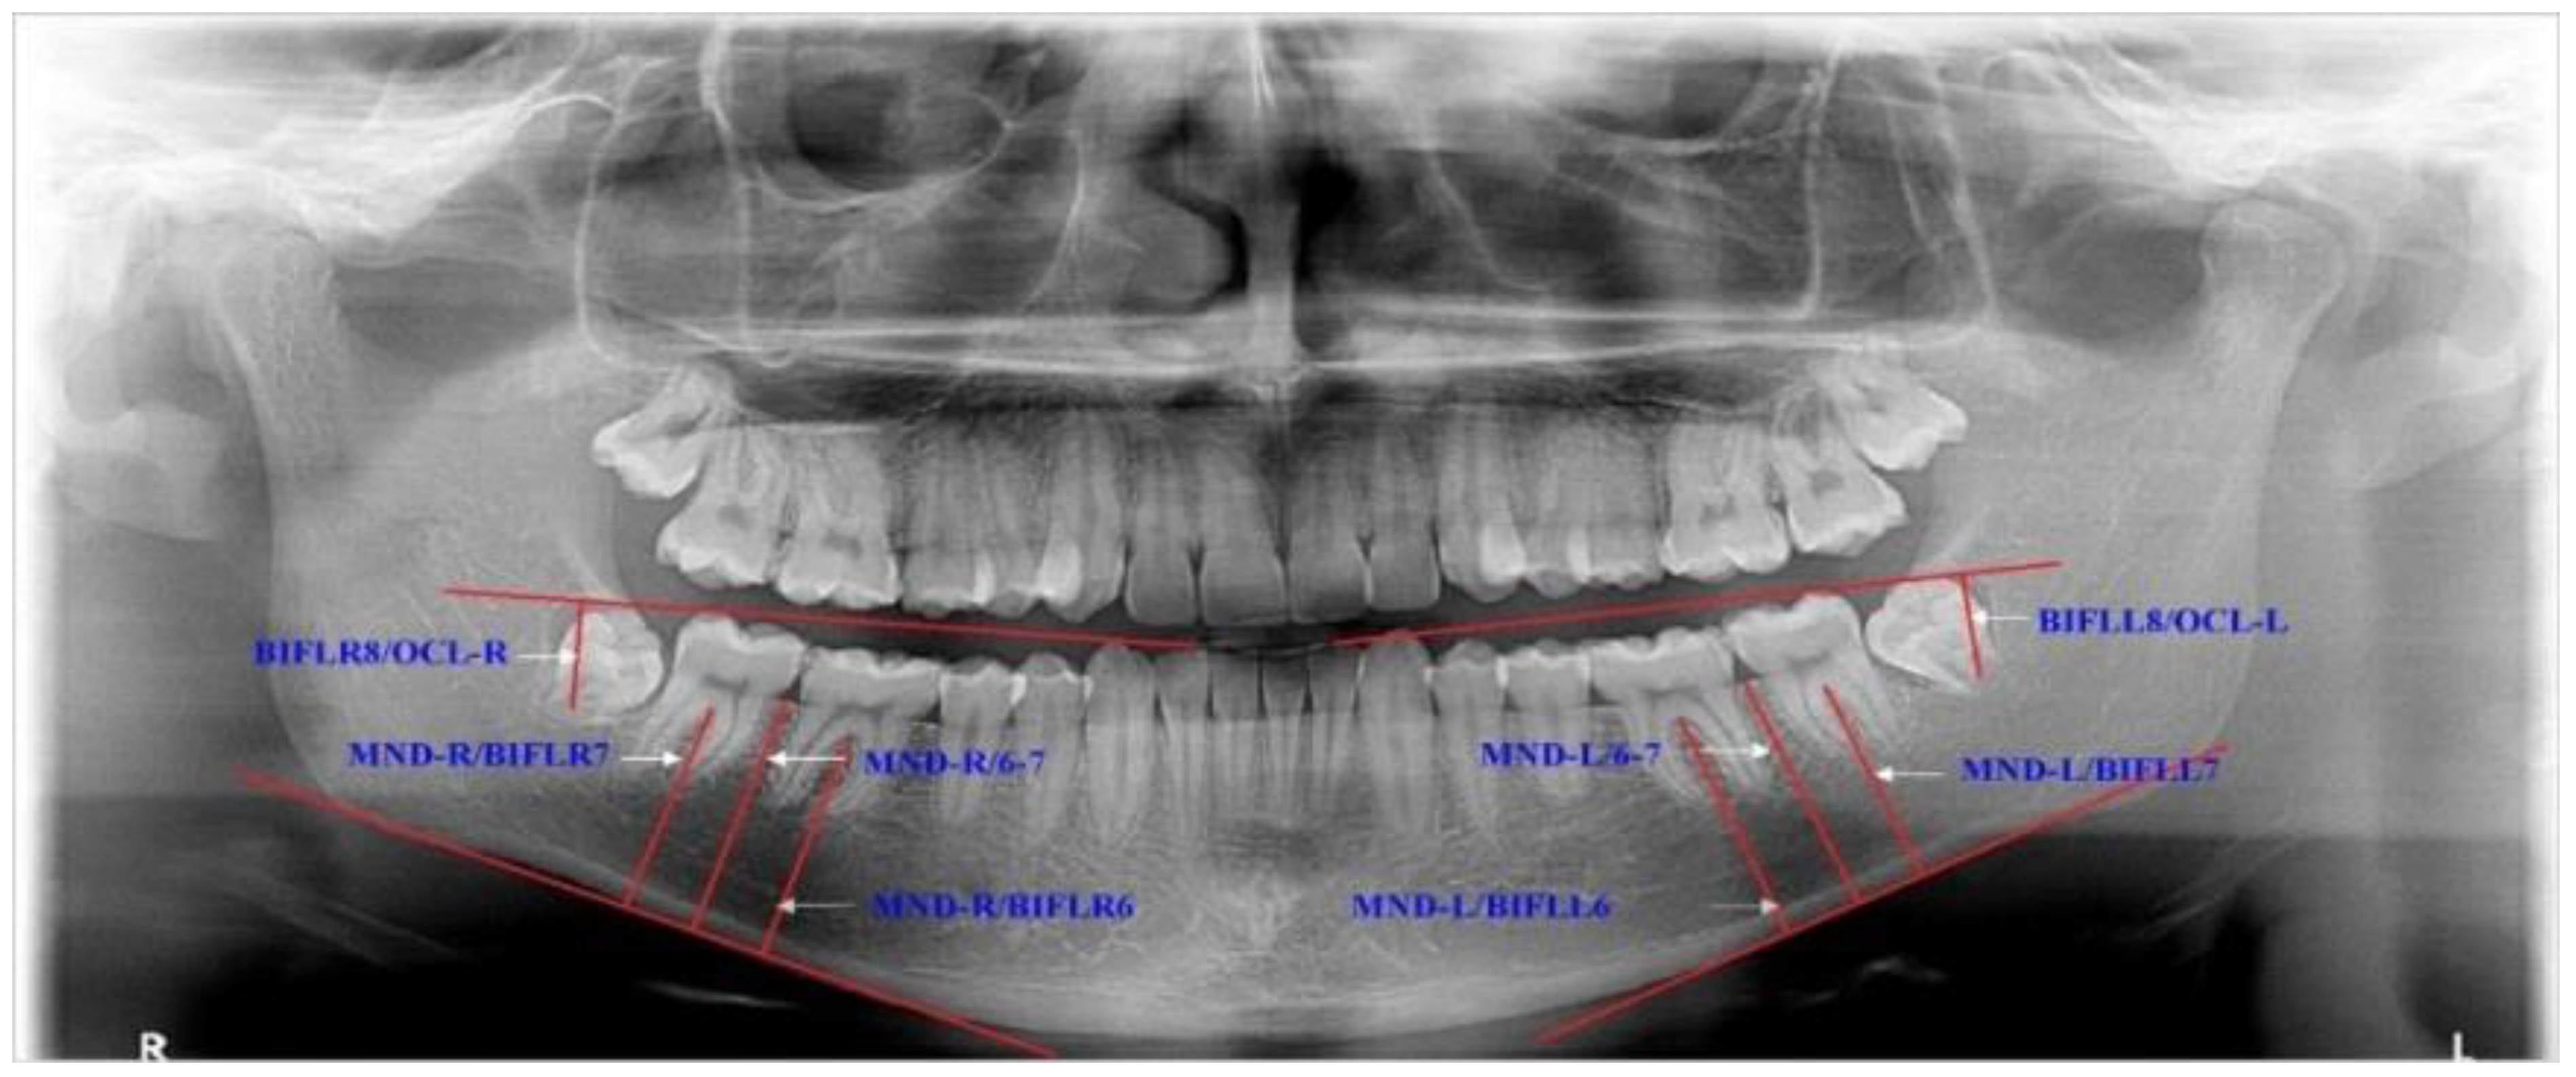

| MND-R/BIFLR6 | ACE | 0.65 | 0.04 | 0.26 | 0.08 | 0.09 | ||

| MND-R/BIFLR7 | ACE | 0.60 | 0.04 | 0.25 | 0.07 | 0.15 | ||

| MND-R/6-7 | ACE | 0.71 | 0.04 | 0.26 | 0.08 | 0.03 | ||

| BIFLR8/OCL-R | ACE | 0.56 | 0.08 | 0.30 | 0.09 | 0.14 | ||

| DLR8/LR7 | ACE | 0.54 | 0.06 | 0.32 | 0.09 | 0.14 | ||